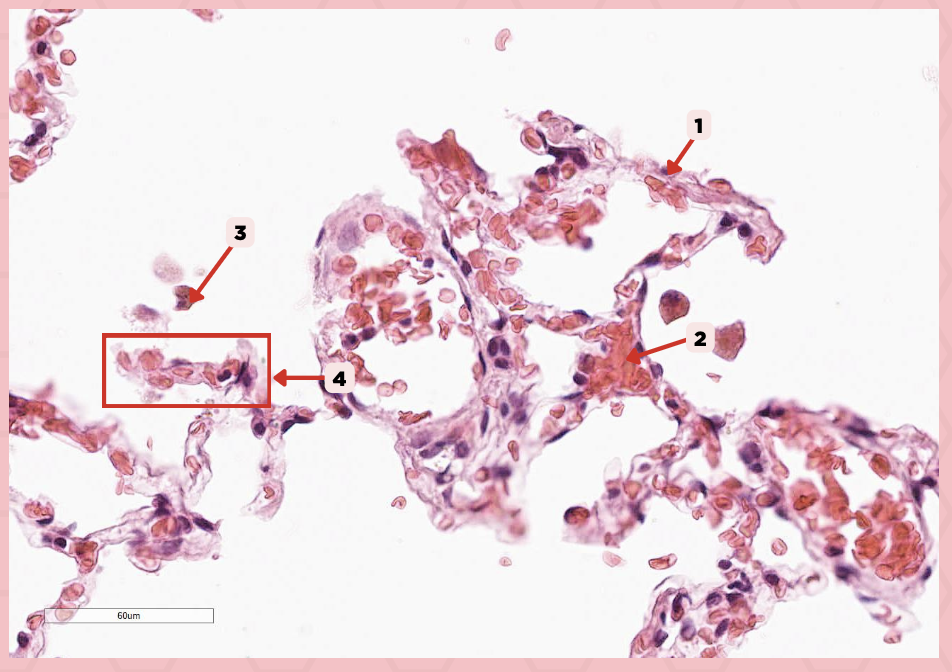

Interalveolar septum

Identify the structure labeled as 1.

Type I alveolar cell

Identify the structure labeled as 2.

Type II alveolar cell

Identify the structure labeled as 3.

Pulmonary Alveolar Macrophages (Dust Cells)

Identify the structure labeled as 4.

Pulmonary Alveolar Macrophages (Dust Cells)

What are the most numerous cells inside the alveoli?

Pneumocyte Type I

Which of the following labeled structures covers 95% of the alveolar surface?

Type I alveolar cell

Identify the structure labeled as 1.

Type II alveolar cell

Identify the structure labeled as 2.

Pulmonary Alveolar Macrophages (Dust Cells)

Identify the structure labeled as 3.

Endothelial Cells

Identify the structure labeled as 4.